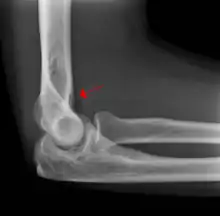

A subtle radial head fracture with associated positive sail sign